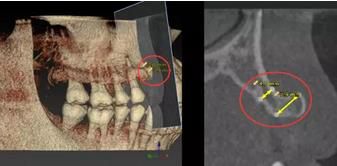

2000年以后,數(shù)字化種植技術(shù)日臻成熟,特別是CBCT(錐形束CT)的普及,使數(shù)字化種植技術(shù)在歐美發(fā)達(dá)國家得到了日益廣泛的應(yīng)用。數(shù)字化種植技術(shù)是指以患者CT影像信息和相關(guān)修復(fù)信息為基礎(chǔ),借助專業(yè)種植設(shè)計(jì)軟件,進(jìn)行術(shù)前診斷和種植方案規(guī)劃;通過牙種植手術(shù)導(dǎo)向模板,將術(shù)前制訂的種植方案準(zhǔn)確應(yīng)用于種植手術(shù)和即刻修復(fù)的全過程,實(shí)現(xiàn)以修復(fù)為驅(qū)動(dòng)的種植手術(shù)。

錐形束CT(CBCT)的普及,精度大大提高;

錐形束CT(CBCT)為重建三圍模型提供精準(zhǔn)數(shù)據(jù)

計(jì)算機(jī)輔助設(shè)計(jì)軟件輔助醫(yī)生定制精準(zhǔn)方案